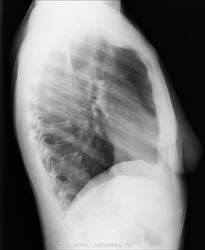

Женщина, 58лет. Жалобы на боли в грудной клетке справа. Анамнеза нет (психиатрический диагноз, неадекватна). Рентгенолога сейчас нет, а решить надо срочно. https://radiomed.ru/sites/default/files/styles/case_slider_image/public/user/19361/206c95351ccb4e9b82361bb74fa6c44a_1.jpg?itok=ZcCSYF5u ID:48039 Mon, 23/12/2013 - 09:40 #1 vadim losevichev Offline Last seen: 7 years 7 months ago Joined: 27.01.2013 - 09:45 Posts: 679 Нормальная картина. Non progrĕdi est regrĕdi. Mon, 23/12/2013 - 10:49 #2 Андрей Юрьевич Offline Last seen: 3 weeks 2 days ago Joined: 16.11.2008 - 22:16 Posts: 18106 Солидарен. Андрей Юрьевич Mon, 23/12/2013 - 11:02 #3 maker4ik Offline Last seen: 9 years 1 week ago Joined: 19.10.2011 - 17:49 Posts: 2682 Ничего плохого не заметила. Mon, 23/12/2013 - 11:07 #4 Ёлка Offline Last seen: 4 years 5 months ago Joined: 04.12.2013 - 11:49 Posts: 44 Спасибо. Mon, 23/12/2013 - 11:18 #5 EvgeniusX-ray Offline Last seen: 12 years 4 months ago Joined: 12.10.2009 - 16:05 Posts: 5 Без видимой патологии ОГК Mon, 23/12/2013 - 11:26 #6 ЕЕЮ Offline Last seen: 2 years 7 months ago Joined: 26.08.2013 - 11:22 Posts: 410 Картина нормы. Mon, 23/12/2013 - 15:08 #7 Сергей Кузьминов Offline Last seen: 1 year 5 months ago Joined: 06.10.2012 - 15:51 Posts: 11813 Норма. Wed, 25/12/2013 - 00:00 #8 Дмитрий Волегов Offline Last seen: 3 years 11 months ago Joined: 22.05.2013 - 00:32 Posts: 1148 Не пропустить быПриложения: С Уважением, Дмитрий. Wed, 25/12/2013 - 00:51 #9 А. Горюнов Offline Last seen: 6 months 1 week ago Joined: 07.10.2012 - 12:12 Posts: 2744 Дмитрий Волегов wrote: Не пропустить бы Исключить пневмоторакс. Анатолий Петрович Wed, 25/12/2013 - 06:51 #10 vadim losevichev Offline Last seen: 7 years 7 months ago Joined: 27.01.2013 - 09:45 Posts: 679 Не вижу разницы.Приложения: Non progrĕdi est regrĕdi. Wed, 25/12/2013 - 10:06 #11 Катенёв Валенти... Offline Last seen: 7 years 5 months ago Joined: 22.03.2008 - 22:15 Posts: 54876 vadim losevichev wrote: Нормальная картина. +1 Wed, 25/12/2013 - 17:45 #12 Ivanaskina Offline Last seen: 8 years 6 months ago Joined: 02.04.2011 - 12:41 Posts: 304 vadim losevichev wrote: Не вижу разницы. Это из-за небольшой асимметрии молочных желез, или укладки. Тоже считаю , что тут норма.

Норма.

Исключить пневмоторакс.

Не вижу разницы.